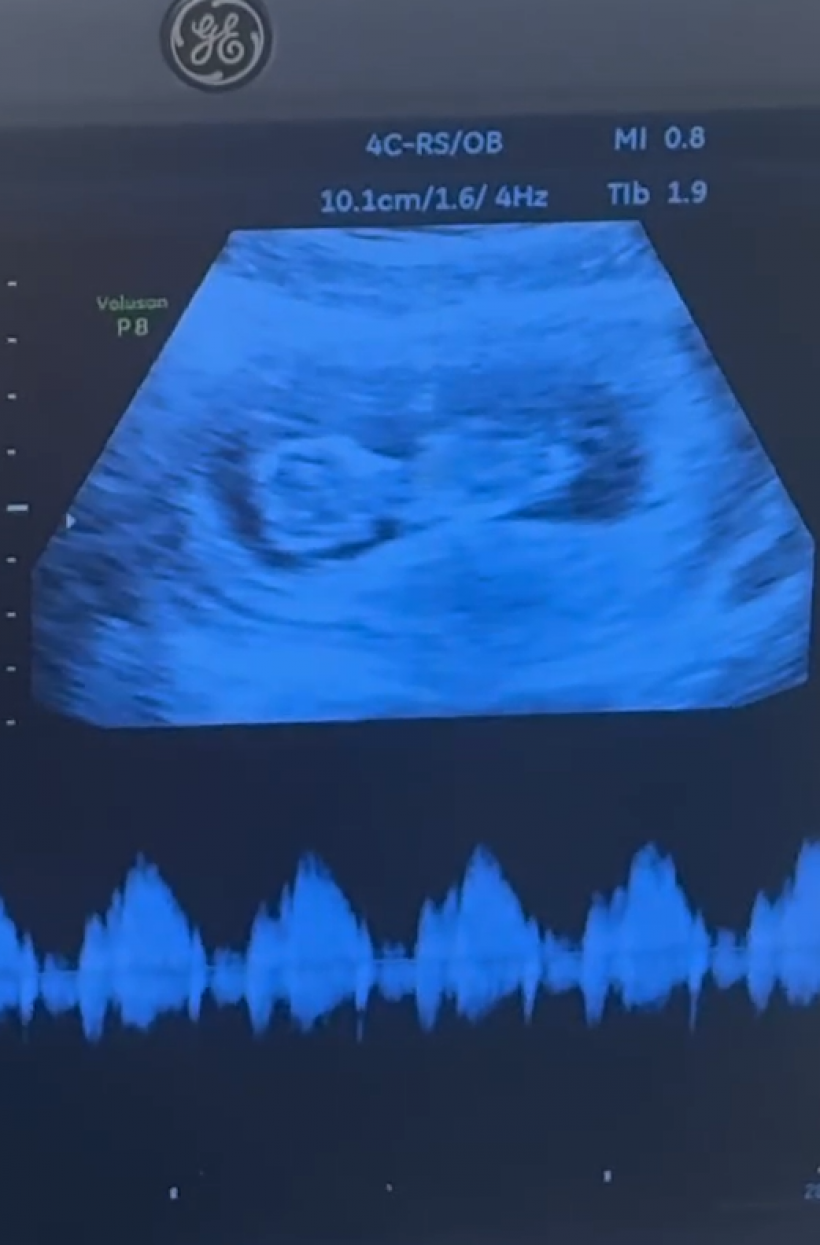

นักร้องวัย 33 ปี บอกว่า ภรรยา บรู๊ค แซนโซน (Brooke Sansone) วัย 26 ปี กำลังตั้งครรภ์ลูกคนแรก และมีกำหนดคลอดในเดือนมีนาคมปีหน้า พร้อมหัวเราะบอกว่า "ผมถูกสั่งห้ามเปิดเผยเพศลูกครับ"

ทั้งคู่แต่งงานกันเมื่อวันที่ 7 กันยายน 2024 และประกาศข่าวดีผ่านมิวสิกวิดีโอเพลง "Changes" ที่บรู๊คปรากฏตัวพร้อมท้องโตอย่างอบอุ่นและน่ารักสุด ๆ